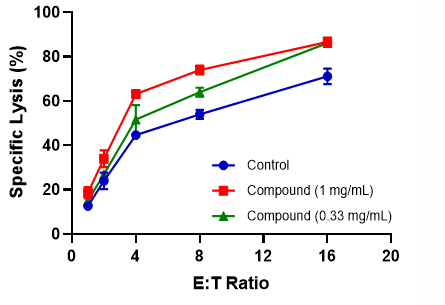

A

Fig 2: (A) FACS gating strategy of different NK cells subsets was used to quantify the proliferation of NK post exposure to Test Compounds. (B) NK specific killing of K562 cells. Test Compound primed NK cells were incubated with K562 cells at different E:T ratio from 0.5:1 to 16:1 for 4 hours (in triplicates) at 37°C in a 95% humidified chamber with 5% CO2. The cytotoxicity of K562 (% Specific lysis) was determined using CTG assay.